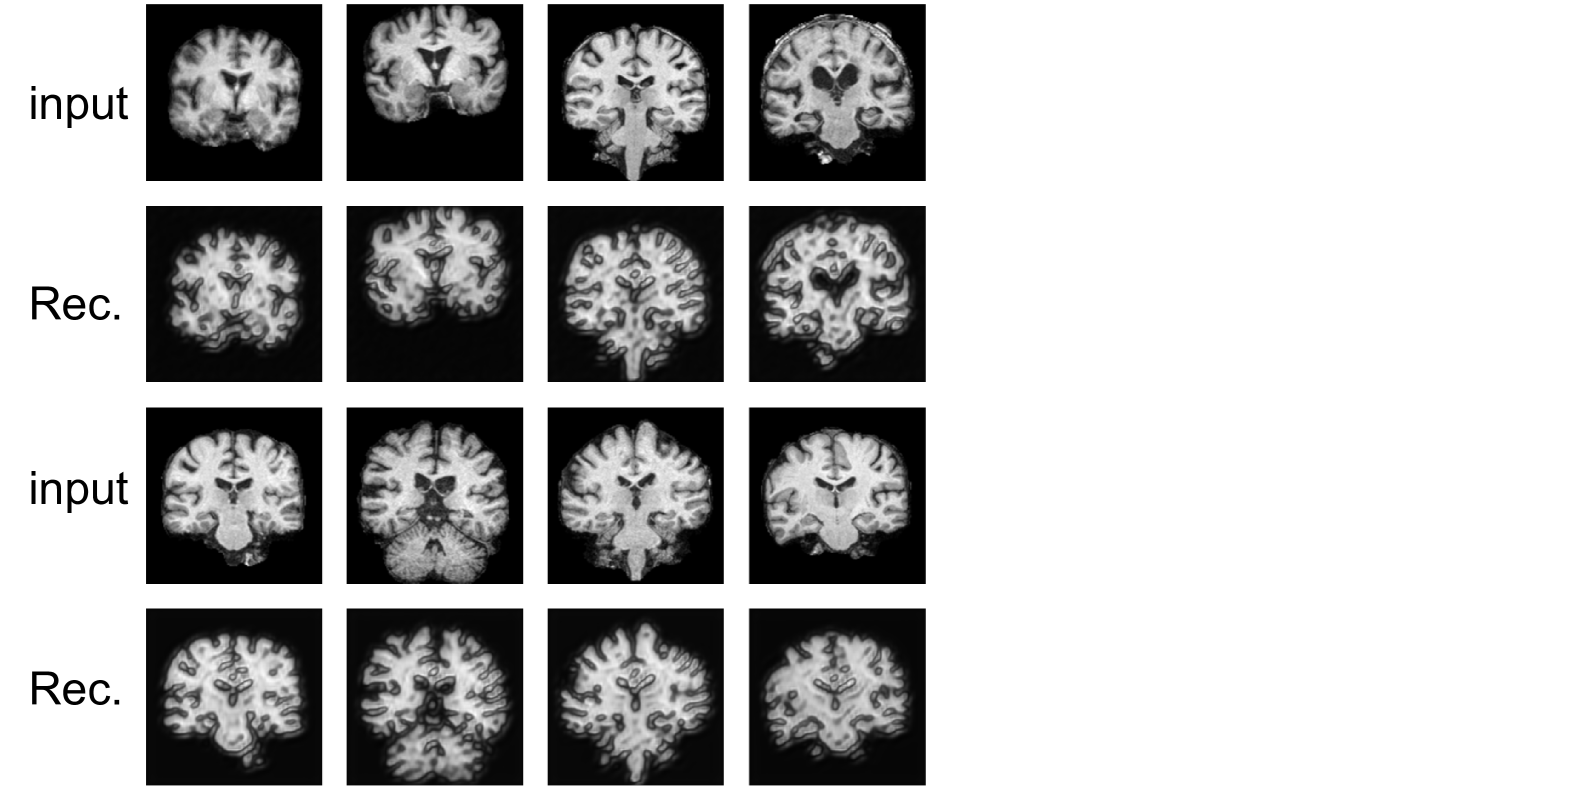

Refer to caption

Figure 9: Visualization of the ablation study results on the OASIS-3 and Baby Brain datasets. Each row represents the brain images generated by different configurations (A, B, C, and D).

Additionally, the visual results of the ablation study, shown in Fig. 9, further support the quantitative findings. For the OASIS-3 dataset, A shows moderate performance but struggles with finer identity details, leading to blurry artifacts. B improves visual consistency and maintains identity features more effectively. C further enhances identity preservation, while D exhibits the most superior performance, achieving accurate age transformation and preserving fine structural details and identity. Similar patterns are observed in the Baby Brain dataset, where D generates the most realistic and precise age transformations, effectively preserving subtle geometric variations and identity features.